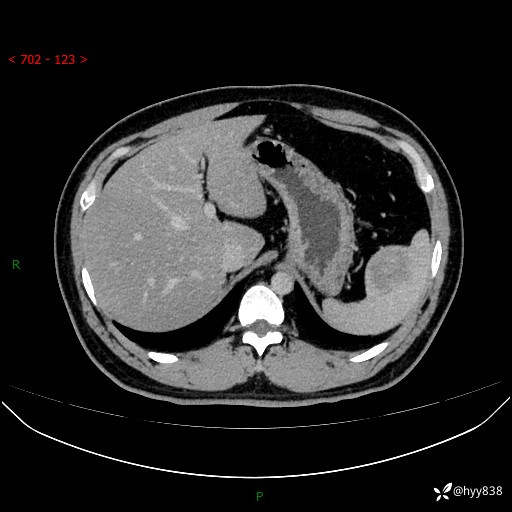

【患者信息】:31岁/男

【主诉】:超声发现脾脏肿物,为进一步诊治来我院,门诊以“脾脏占位”收入院

【检查】:上腹部CT平扫+增强